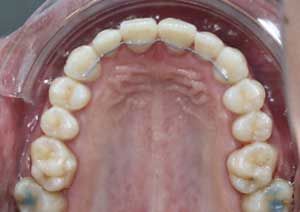

Traitement : Une ingression des molaires maxillaires avec une égression contrôlée du secteur antérieur a été réalisée à l’aide des arcs dits “Rocking Chair”, associés à des élastiques antérieurs portés de canine à canine, à droite et à gauche.

Cette mécanique permet de corriger la béance antérieure tout en conservant un contrôle précis de la position des dents antérieures et postérieures.

Après